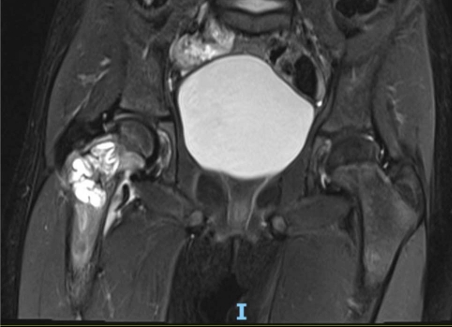

Complete bone union was achieved, and hardware removal was performed.

1 Year After Hardware Removal

The femoral neck remodeled to a normal neck-shaft angle.

At final follow-up, the patient had:

• No joint stiffness

• Full range of motion

• No pain

• No limp